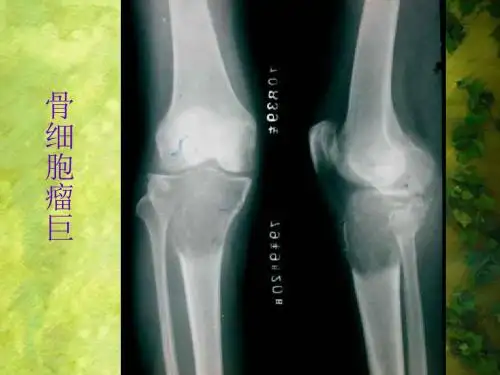

• 偏心性 • 巨细胞瘤、软骨母细胞瘤、动脉瘤样骨囊肿、 • 非骨化性纤维瘤,和罕见的软骨黏液样纤维瘤均位于骨的偏心部位。